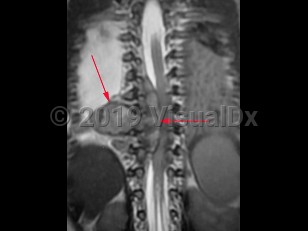

Neuroblastoma is a neuroendocrine tumor that arises from neural crest cells. It is the most common solid tumor of infancy and childhood; typical age of onset is less than 3 years old. The adrenal glands are the most frequent site of origin, but this tumor can be found anywhere along the sympathetic nervous system chain including the neck, chest, abdomen, or pelvis. Presenting symptoms depend on the site of origin and areas of metastasis if present but may be nonspecific including fatigue, fevers, anorexia, abdominal pain, or joint or bone pains. Less common symptoms include weakness, ataxia, chronic diarrhea, hypertension, or shortness of breath. The presence of Horner syndrome or opsoclonus-myoclonus syndrome in children should prompt evaluation for this type of tumor. Rarely, neuroblastoma may be an incidental finding on radiology.